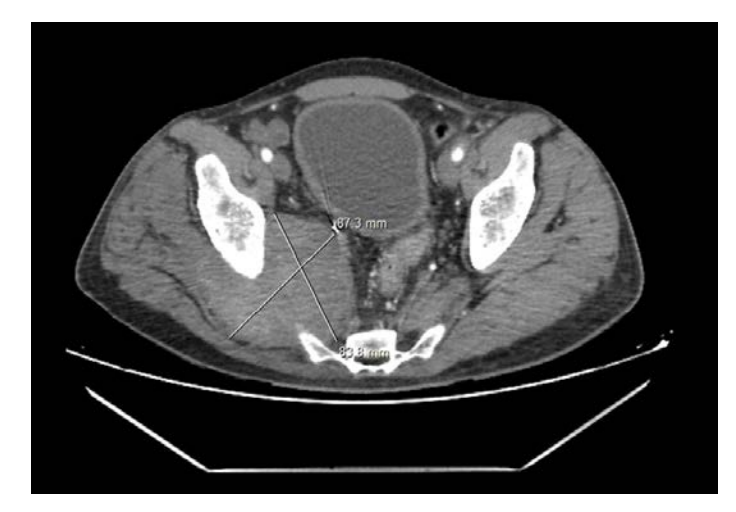

The first patient was a 44-year-old male without medical history, who developed an acute pain the day following an intramuscular injection in the right gluteal muscles, with paraesthesia and paresis of the right inferior limb. Three months later the patient presented in the emergency department due to worsening pain. Computed tomography scan (CT scan) identified a pseudoaneurysm in the right gluteal region arising from a branch of the right internal iliac artery which was most likely the inferior gluteal artery (IGA) (Figure 1). We performed a cross-over catheterisation and angiography of the right internal iliac artery which showed a contrast leakage of the IGA (Figure 2). We performed an embolization of the pseudoaneurysmal sac using 15x20 cm and 20x30 cm coils and embolization of the origin of the IGA using 12x30 cm and 10x20 cm coils (Figure 3). A CT scan was done 48 hours after and showed a profound hematoma of the right gluteal region without signs of contrast media extravasation. The day after, the patient benefited from drainage of the hematoma through a right retroperitoneal anterior incision (Figure 4). Transfusion of 2 units of blood was necessary after surgery. He had an uneventful recovery.